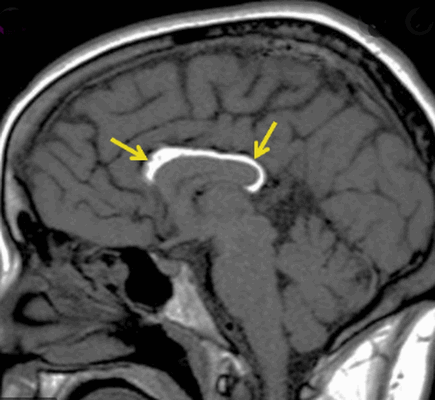

Липома мозолистого тела на МРТ (указана стрелками)

Липома на МРТ головного мозга

МРТ, Т1-ВИ sag Перикаллезная липома